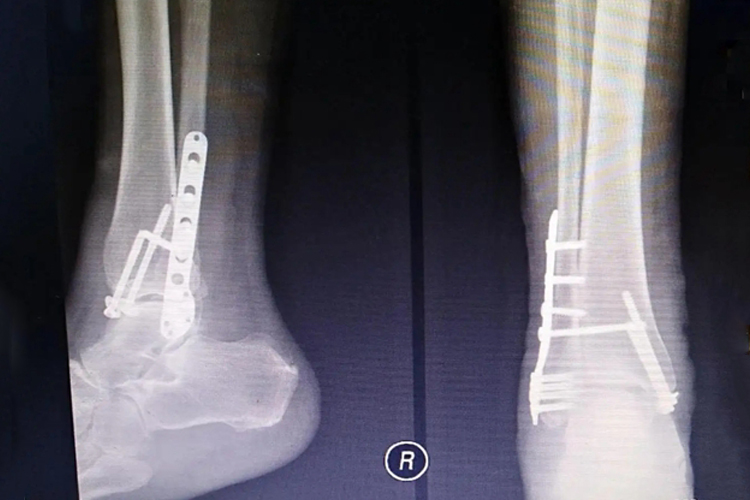

脚踝骨折打钢钉是切开复位、内固定的一种方法,可通过X线进行观察。脚踝骨折多由间接暴力引起,打钢钉后可使关节更加稳定。

Ⅰ型骨折为双踝骨折,为恢复韧带张力,一般均应行切开复位,松质骨螺钉、钢板内固定。

Ⅱ型骨折即三踝骨折,内踝骨折采用松质骨螺钉内固定,外踝骨折常采用钢板固定。影响胫骨1/4-1/3关节面的后踝骨折也需用松质骨螺钉或支撑钢板内固定。